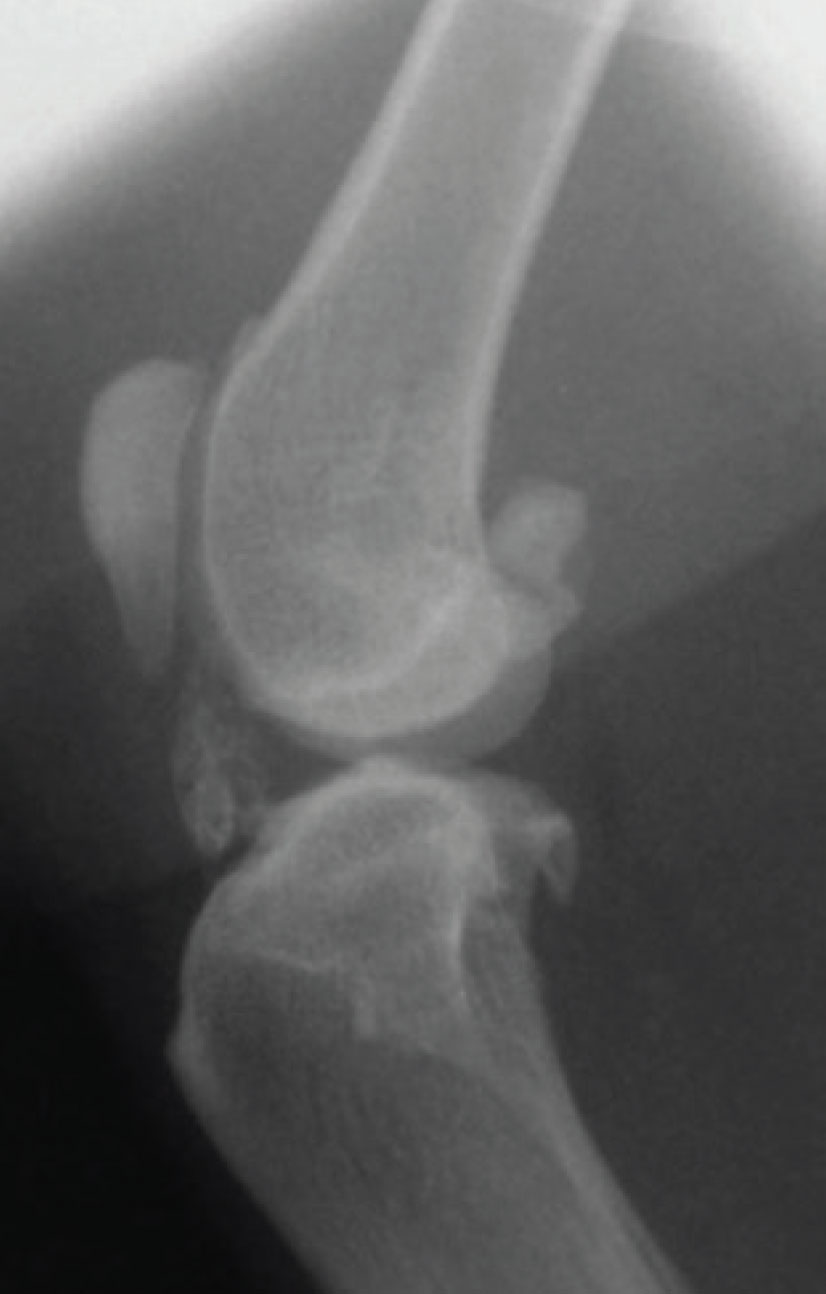

Although the combination of appropriate clinical signs and physical examination findings may lead you to be fairly certain a cat has OA, it is ideal to try to confirm your suspicions by seeing radiographic changes. The primary radiographic change associated with osteoarthritis is the presence of periarticular osteophyte formation, although this is not always present or easily identifiable in every case. It is important to appreciate that osteoarthritis may be present in the absence of obvious radiographic changes. Contrarily, the presence of radiographic changes does not always correlate with clinical signs of OA nor the degree of pain suffered. Occasionally, cats develop excessive periarticular mineralisation and ossified bodies adjacent to their joints, particularly in the stifle joint (see Figure 4).

Figure 4: Mineralisation of the intra-articular structures in the stifle of a seven-year male neutered cat. There is also mild periarticular osteophytosis of the stifle with new bone on the proximal pole of the patella and trochlear ridge.